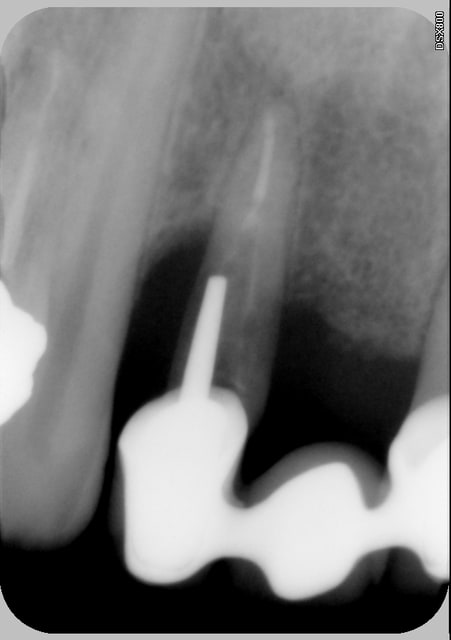

C'est quoi la proba d'avoir une deuxième bio à 5 canaux en 2 semaines?

(la radio excentrée est dégueulasse, mais ça montre les doubles courbures, quelques peu minimisées par l'angulateur...